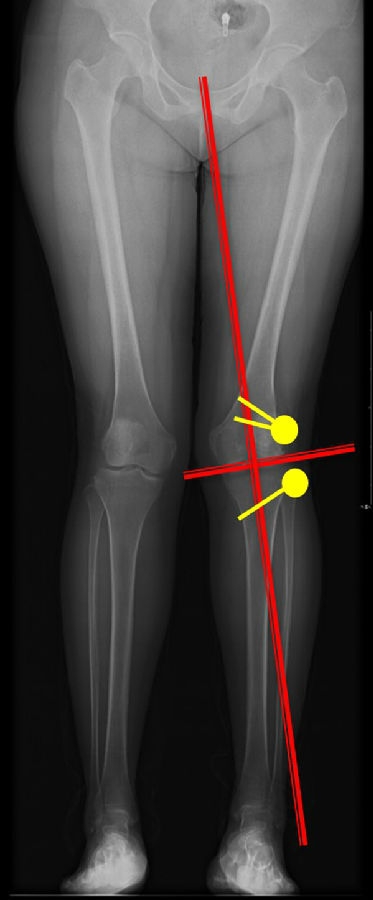

患者二,女性,膝外翻,膝外侧疼痛。通过做畸形分析后发现,该患者同时存在股骨侧畸形、胫骨侧畸形和关节内畸形(LDFA=82°,MPTA=104°,JLCA=6°)。

对于这类病人如何进行术前设计的关键点就在于目标力线应如何设计。要在骨性截骨的时候纠正骨性畸形,关节内畸形要通过关节内的方法解决。因为JLCA不平行,所以要同时画股骨侧关节线和胫骨侧关节线,并垂直于股骨侧关节线做出股骨侧目标力线,垂直于胫骨侧关节线做出胫骨侧目标力线。

根据各自目标力线,分别计算股骨内侧闭合和胫骨内侧闭合角度。

此患者股骨内侧闭合6°,经股内侧闭合13°。